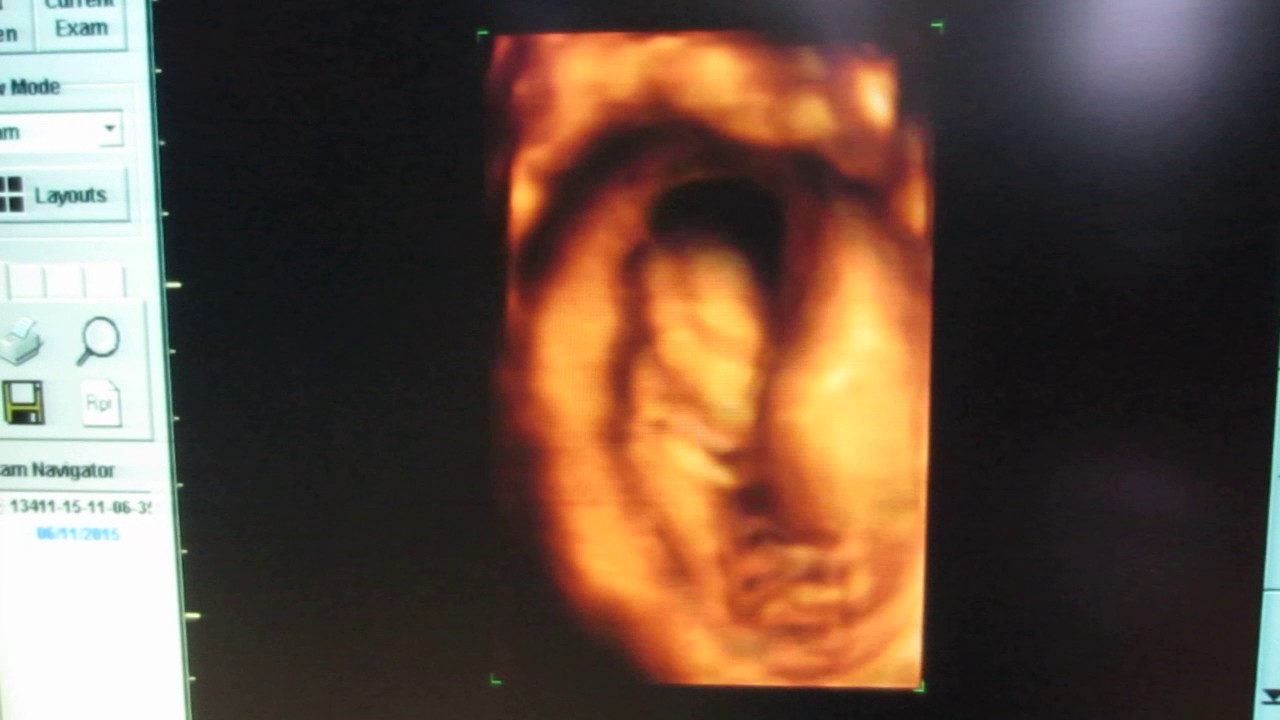

Если сделать УЗИ на девятой неделе беременности, оно покажет, что плод хорошо визуализируется в полости матки и окружен околоплодными водами. Такое обследование позволяет зафиксировать как двигается ребёнок, установить частоту сердцебиения, которая должна соответствовать 120-140 ударам в минуту.

Также УЗИ-исследование помогает дать правильную оценку развитию плода, подтвердить сроки беременности. А информацию об этом можно получить с помощью замеров крохи от копчика до темени. Такие измерения называют копчиково-теменными или КТР плода, и на данном сроке он соответствует 20-22 мм, но 15-30 мм тоже является нормой.

Отделение ультразвуковой диагностики экспертного уровня «НИКА СПРИНГ» оборудовано инновационным аппаратным парком, а штат укомплектован высококвалифицированными специалистами. Наши аппараты УЗИ способны показать объемную 3Д картинку, а также 4Д (в движении, как видео) — при беременности это позволяет наблюдать плод наиболее наглядно, повернуть изображение под таким углом, чтобы сделать доступными для врача те части тела будущего ребенка, которые при обычном исследовании не видны.

В 4D уже на ранних сроках можно различить пол, а на поздних – увидеть, как малыш зевает, улыбается, открывает глаза, или даже рассмотреть личико.

УЗИ 9 недель

Этот период, вероятно, является одним из самых приятных периодов вашей беременности. Вас отправят на УЗИ, где вы сможете услышать сердцебиение вашего малыша! Это УЗИ также содержит важную информацию, такую как состояние плода, матки и, самое главное, продолжительность вашей беременности.

Если все пойдет хорошо, сердцебиение вашего ребенка будет около 130-150 ударов в минуту. Также УЗИ определит подвижность вашего малыша. Тем не менее, вы, вероятно, некоторое время не будете чувствовать движения своего тела в животе.